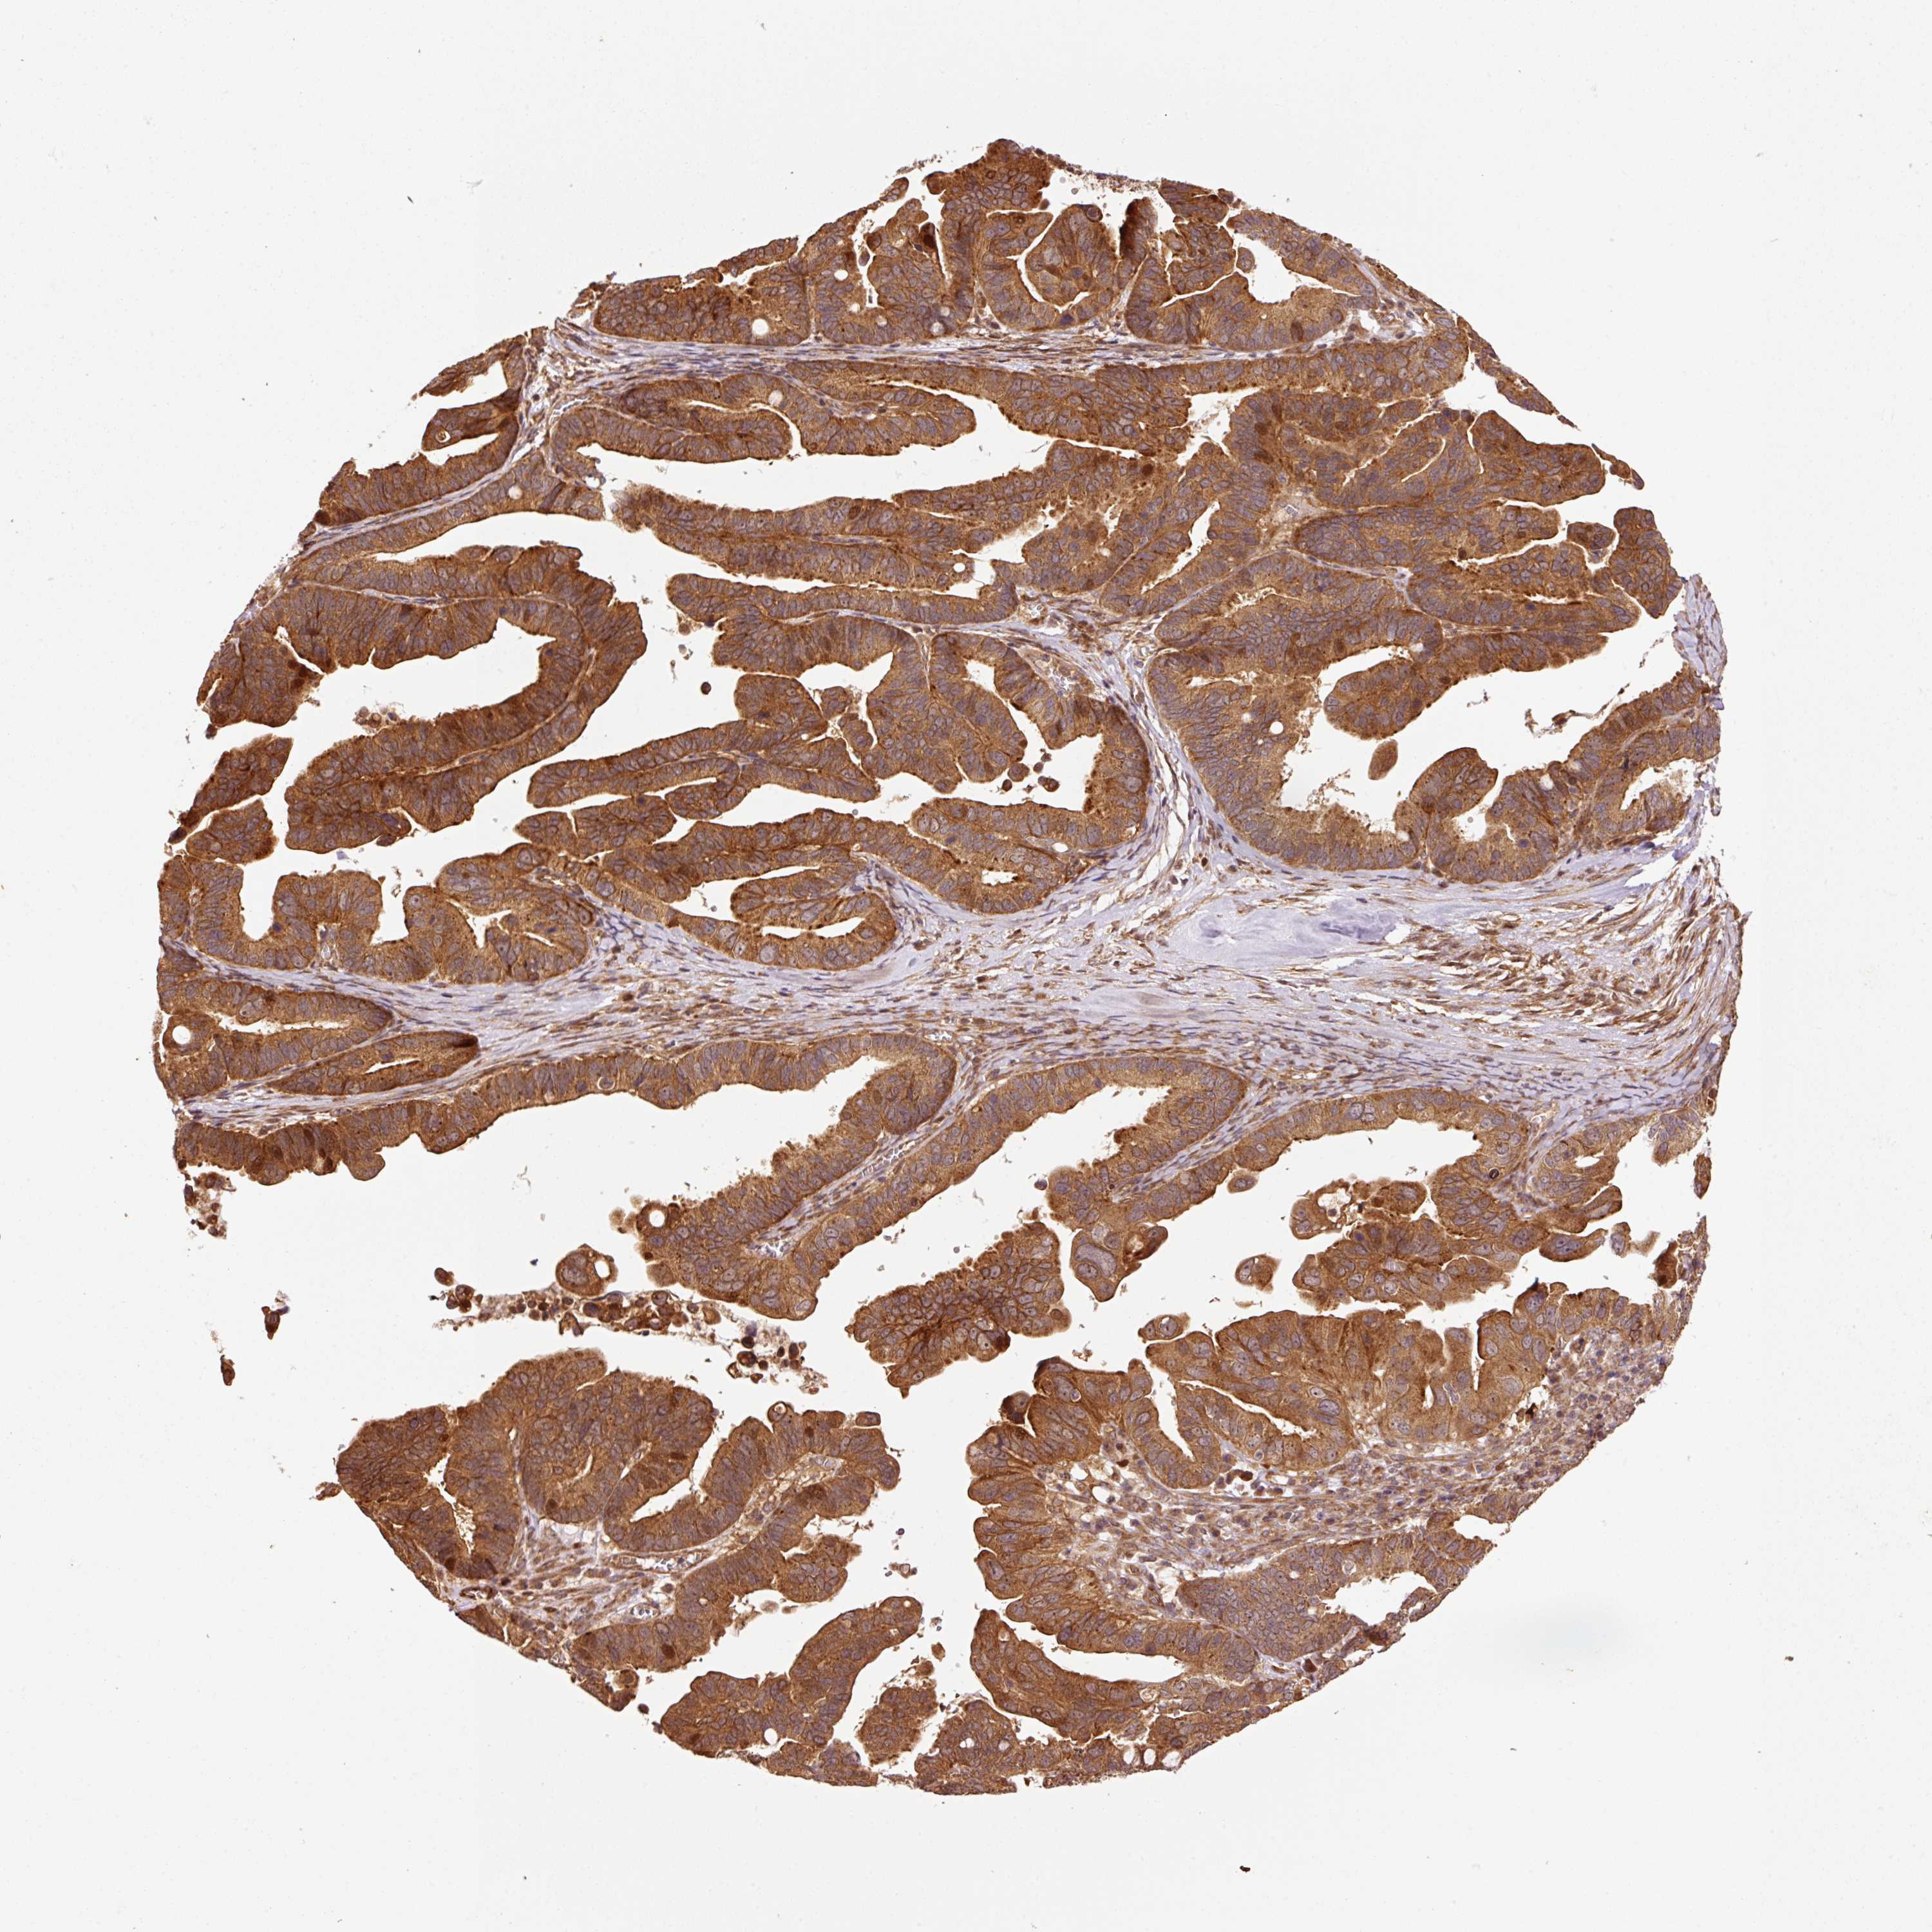

OVARIAN CANCER - Protein expressioni

A mouse-over function shows sample information and annotation data. Click on an image to view it in a full screen mode. Samples can be filtered based on level of antibody staining by selecting one or several of the following categories: high, medium, low and not detected. The assay and annotation is described here.

Note that samples used for immunohistochemistry by the Human Protein Atlas do not correspond to samples in the TCGA dataset.

Antibody stainingi

Antibody staining in the annotated cell types in the current human tissue is reported as not detected, low, medium, or high, based on conventional immunohistochemistry profiling in selected tissues. This score is based on the combination of the staining intensity and fraction of stained cells.

Each image is clickable and will lead to virtual microscopy that enables deeper exploration of all samples and also displays staining intensity scores, fraction scores and subcellular localization as well as patient and tissue information for each sample.

Antibody HPA051433

Cystadenocarcinoma, serous, NOS

Carcinoma, endometroid

Cystadenocarcinoma, mucinous, NOS

Carcinoma, NOS